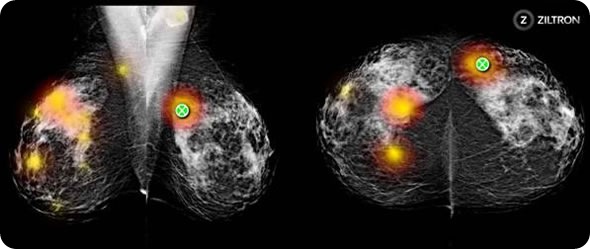

Figure 2

Figure 2. Screenshot of heat-map showing variance in opinion amongst 140 Australian radiologists. The actual cancerous lesion underlies the green marker. All other regions are normal.